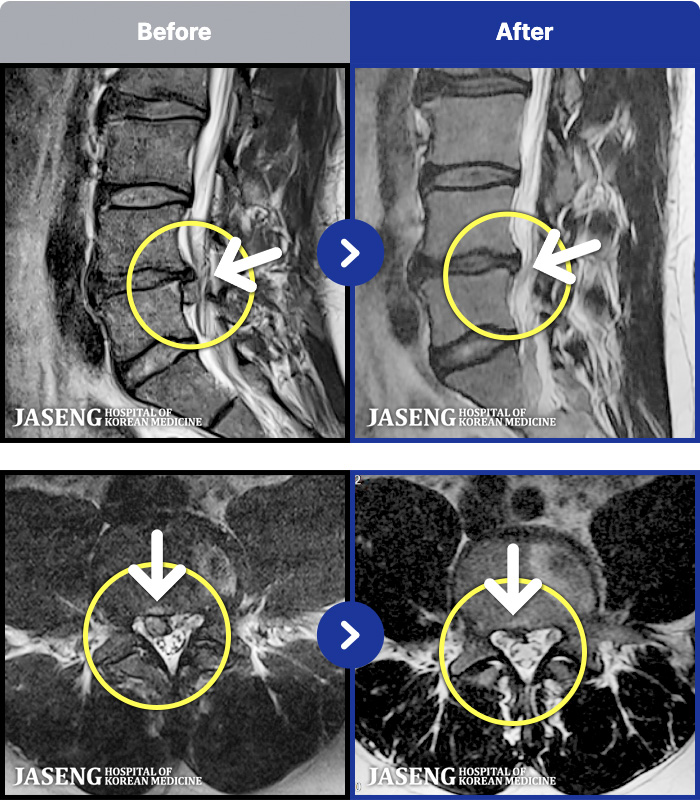

54 MRI ũ ʸ Ȯϼ.

[ϻ] 24.07.25~25.08.01